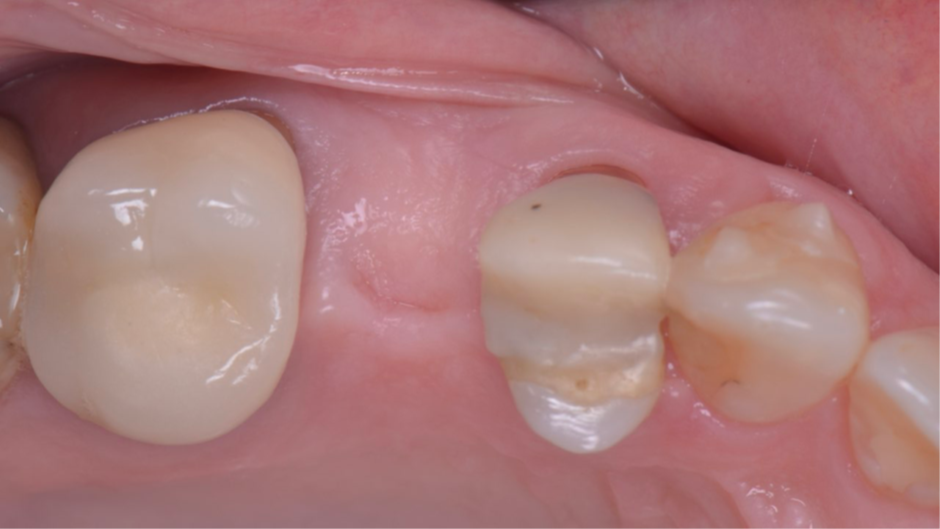

Após a finalização, os dentes adjacentes foram preparados e também receberam coroas provisórias, e a coroa sobre implante provisória foi parafusada no pilar Ideale (Figura 15) usando uma combinação de pressão digital e apertamento do paciente em um rolo de algodão. A isquemia dos tecidos moles peri-implantares pode ser observada, e geralmente desaparece em até 20 minutos. A coroa sobre implante provisória deve ser deixada por um período mínimo de um mês para permitir o adequado condicionamento dos tecidos moles peri-implantares 11,12 (Figura 16). Foi necessário um exame periódico para garantir que a higiene bucal adequada fosse mantida. Após dois meses, quando a mucosa condicionada se estabilizou 13, foi realizado um escaneamento intraoral (Figura 17) para a confecção das coroas definitivas (Figura 18). As coroas definitivas foram fabricadas fresadas em zircônia pura, e após instaladas (Figura 19), o resultado estético e funcional ficou muito favorável (Figura 20).

Figura 16 – Condicionamento dos tecidos moles peri-implantares após um mês.